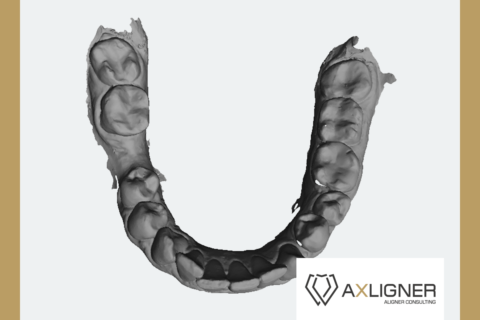

Konsultacja zawierała analizę cyfrowego planu leczenia oraz na dodatkowe zlecenie lekarza przeprowadzono jednocześnie pisemną analizę zdjęcia panoramicznego pacjenta.

Wykonano ewaluację zaproponowanych sekwencji ruchów zębowych w dostarczonym planie 3D jednej z polskich firm nakładkowych. Opisano jak kształt i wielkość przemieszczanych zębów może wpłynąć na skuteczność kliniczną zaplanowanego leczenia.